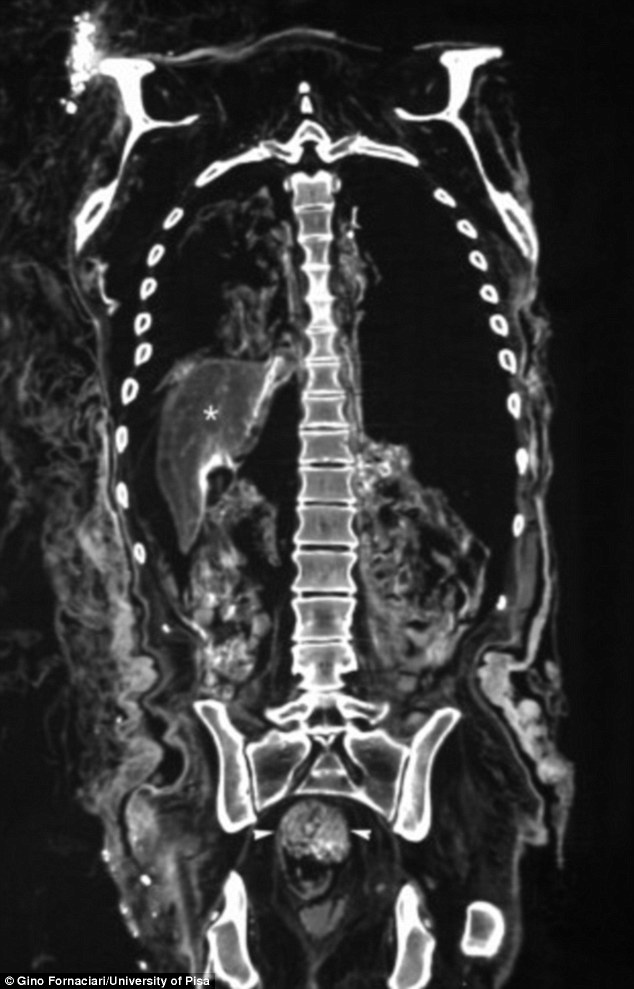

Tietokonetomografia (TT) ja röntgentutkimus paljastivat ruhtinaan ruokatorvessa oksennusta, kyynärpäissä ja lantiossa kulumia, ja sisäelimissä mahdollisia merkkejä tuberkuloosista ja kirroosista. Vatsan TT-kuvaus paljasti suolistossa ulosteiden jäänteitä, joten niistä otettiin näyte siitepölytutkimusta varten. Siitepölytutkimuksessa ulosteessa havaittiin kamomillaa ja mulperia, sekä tutkijoiden yllätykseksi myös erittäin myrkyllistä sormustinkukkaa. Toksikologinen analyysi vahvisti siitepölytutkimuksen tuloksen, sillä sekä ulosteessa että maksassa oli myrkyllisiä pitoisuuksia digoksiinia ja digitoksiinia, jotka ovat sormustinkukan sisältämiä aineita. Kukasta uutettua nestettä on mitä ilmeisimmin annettu Cangrandelle suun kautta, luultavasti suolistovaivojen lääkinnän varjolla.